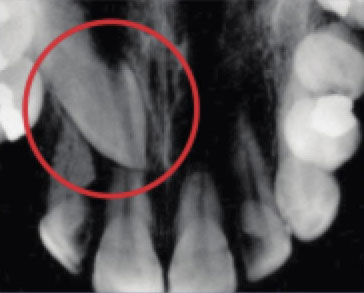

of the mouth. - Periapical X-Ray shows a few complete teeth and their roots and the jawbone in a certain

This periapical x-ray shows the top of a molar unable to reach the surface (impacted).